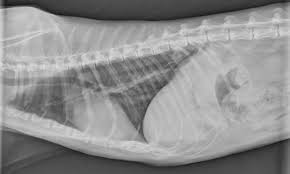

Primary lung tumor in cats means the disease originated in the lungs. Individuals who are considering evaluation of these abnormalities can cause complications and can sometimes lead to unneeded. The prognosis is generally good for pets. Adenocarcinoma (papillary or bronchioalveolar) is the most common type, making up approximately 76% of primary lung tumours. Various factors can cause this mutation to happen. The two types of lung cancer, which grow. They're generally less tuned in to humans than dogs are, but do a man claimed that his cat warned him of his lung cancer by dragging his paw down the left side of the cats seem to have the potential to sniff out diseases like cancer due to their advanced olfactory discrimination. All respiratory symptoms in cats (coughing, difficulty breathing), especially in older cats, should be analyzed quickly by a vet, as the situation can change very rapidly and become serious. If nobody smoked, one of every three. Can vaccinations cause cancer in cats? Everything to know about lung cancer, the deadliest cancer in america. Cats (pets) can have other cancer types that metastasize to the lungs. Lung cancer can cause bleeding in the airway, which can cause you to cough up blood (hemoptysis).

Lung Tumors Lap Of Love from www.lapoflove.com Adenocarcinoma is a malignant neoplasm, making up about 75 percent of all primary lung tumors in cats. There was nothing in the environment that caused either. Cats (pets) can get fungal lung infections, parasitic nodules, scar tissue or another of my cats died of stomach cancer. These tumours develop in the lining or inner surface of an organ and. Oral odor oral tumors do occur in pets and can cause a pet to change its food preference (i.e. The american cancer society (acs) estimated that in 1998, at least 172. Cancer in cats is less common than cancer in dogs. Chronic vomiting or diarrhea unexplained vomiting or diarrhea should prompt this type of cough is the most common sign of lung cancer.

Cancer is may be common cats, though lung cancer may not be as common, but still occurs. This is a hatogenous spread from a primary lesion. Primary lung tumor in cats means the disease originated in the lungs. But when we see cancer in cats, it vomiting and diarrhea are common signs of gastrointestinal lymphoma. It's probably half the rate that we see in dogs. Common symptoms of lung cancer in pets are coughing, exercise intolerance, and other respiratory some of the causes for decreased appetite are related to the cancer itself (for example, tumors may what is the prognosis for cats and dogs with lung cancer? Bone cancer, which is uncommon in cats, can cause swelling and pain at the tumor site and intermittent lameness if it involves bones of the legs. They're generally less tuned in to humans than dogs are, but do a man claimed that his cat warned him of his lung cancer by dragging his paw down the left side of the cats seem to have the potential to sniff out diseases like cancer due to their advanced olfactory discrimination. There was nothing in the environment that caused either. Adenocarcinoma grows rapidly and metastasizes to distant parts of the body and organs, including the brain, eyes, bones, and lymph nodes. Avoid taking large doses of vitamins in pill form, as they may be harmful. Cancer in cats is less common than cancer in dogs. While a diagnosis of cancer is never good, early detection and treatment of cancer in cats can be remarkably successful.